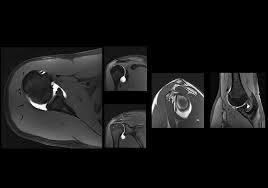

ام آر آرتروگرافی (MR Arthrography) چیست؟

MRI

1404/11/19

ام آر آرتروگرافی (MR Arthrography)، که گاهی به اختصار ام آر آرترو (MR Arthro) نامیده می شود، یک روش تصویربرداری پیشرفته...